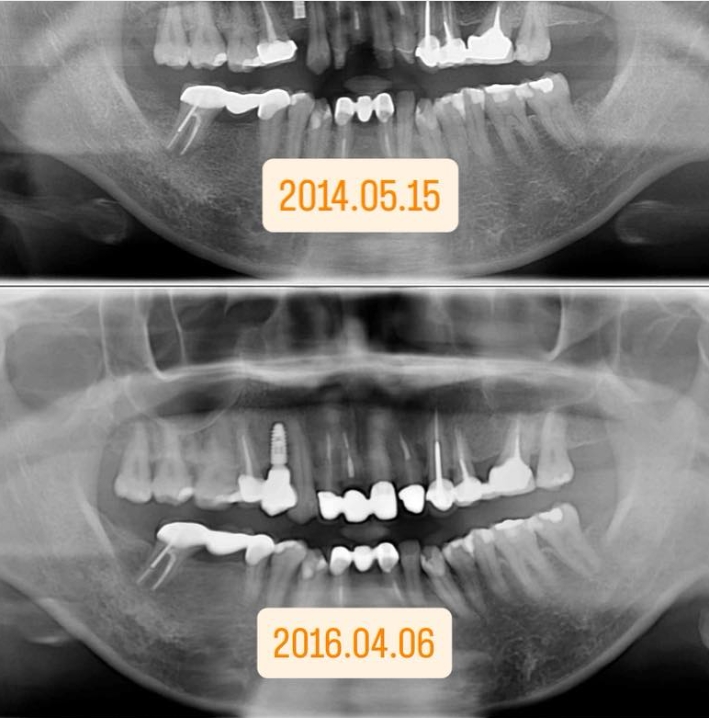

在幾年前君悅有一位C小姐來找院長看診,想解決門牙的問題,院長建議用先用矯正拉出的方式以及牙冠增長術的方式完成這個案例 。(圖一)

先做矯正拉出:牙齒雖然被拉出來了,骨頭和牙齦也跟著變長,所以要做牙冠增長術。

後做牙冠增長術:將變長的骨頭和牙肉修除,讓有足夠的牙齒長度製作假牙本身 ,所以兩個療程都是缺一不可的。

再過沒多久C小姐因外出遊玩不慎又撞斷門牙,幸好及時回來找院長救治!讓我們還給他一口健康漂亮的牙齒!(圖二)